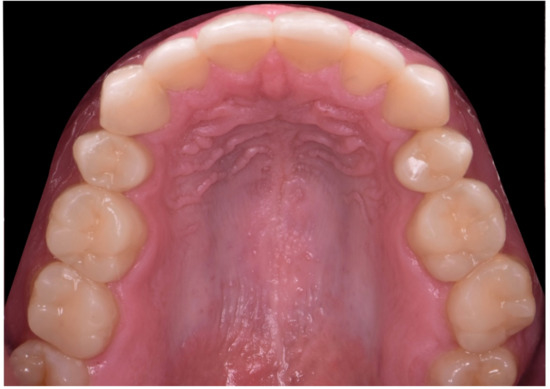

2.2. Restorative Phase